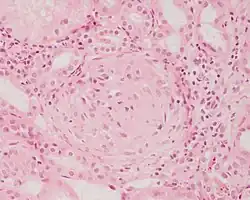

![]() |

Granulation tissue | Micrograph showing proliferating capillaries, fibroblasts and acute inflammatory cells. | Category: Histopathology of granulation tissue | Granulation tissue |